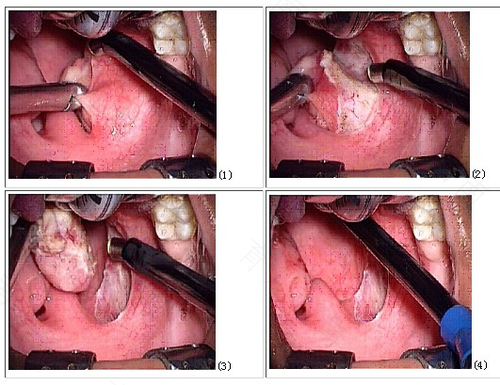

慢性咽喉炎常见症状有咽干、咽部异物感、刺激性咳嗽、反复咳痰等,部分患者主诉刷牙的时候出现恶心、反酸、烧心等表现。临床上,一般会对慢性咽喉炎进行喉镜检查,在内镜下会发现舌根增生、会厌囊肿、声带占位性病变、咽喉反流等情况。不同情况的患者,往往有不同的症状,针对不同症状,往往采取不同的治疗措施。